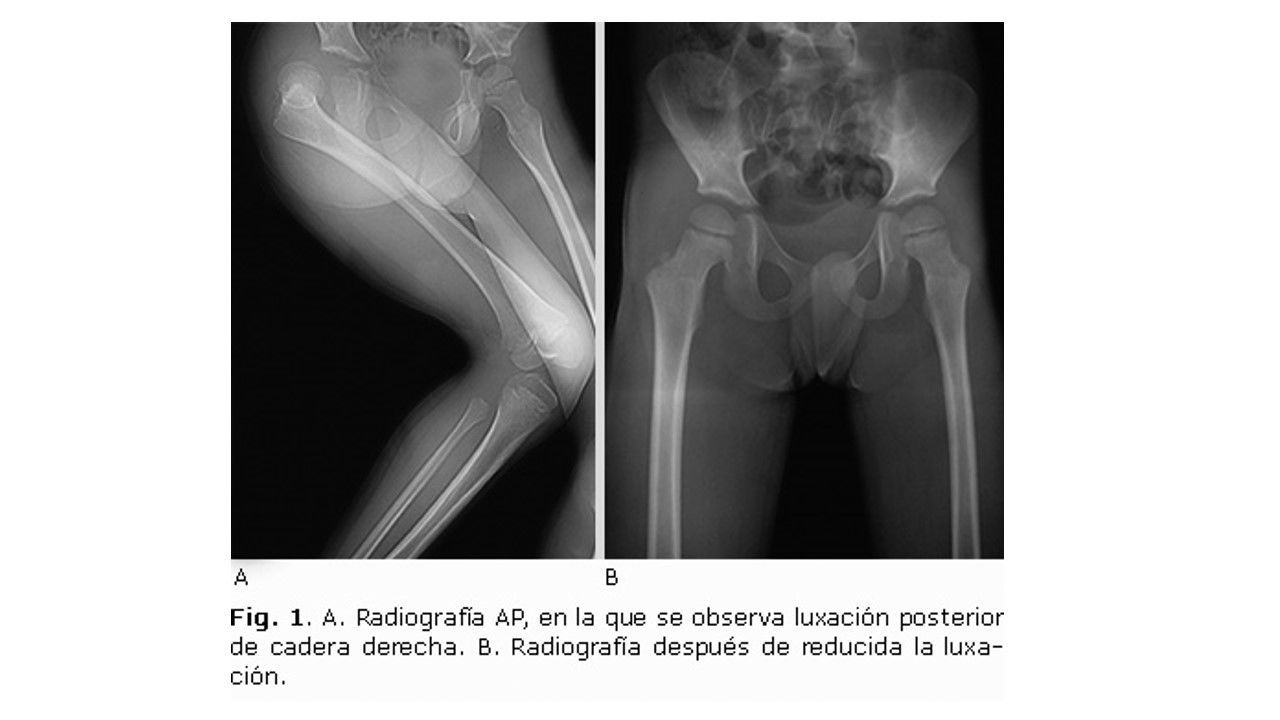

1. Radiografías: AP de pelvis con ambas caderas y oblicua de cadera afectada; y proyecciones tipo: JUDET, ALAR Y OBTURATRIZ

1. En la luxación posterior el muslo está en actitud de flexión, aducción y rotación interna